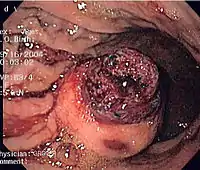

CT scanning is often undertaken (see the radiology section).

The definitive diagnosis is made with a biopsy, which can be obtained endoscopically, percutaneously with CT or ultrasound guidance or at the time of surgery. A biopsy sample will be investigated under the microscope by a pathologist physician. The pathologist examines the histopathology to identify the characteristics of GISTs (spindle cells in 70-80%, epitheloid aspect in 20-30%). Smaller tumors can usually be confined to the muscularis propria layer of the intestinal wall. Large ones grow, mainly outward, from the bowel wall until the point where they outstrip their blood supply and necrose (die) on the inside, forming a cavity that may eventually come to communicate with the bowel lumen.

When GIST is suspected—as opposed to other causes for similar tumors—the pathologist can use immunohistochemistry (specific antibodies that stain the molecule CD117 [also known as c-KIT] —see below). 95% of all GISTs are CD117-positive (other possible markers include CD34, DOG-1, desmin, and vimentin). Other cells that show CD117 positivity are mast cells.

If the CD117 stain is negative and suspicion remains that the tumor is a GIST, the newer antibody DOG-1 (Discovered On GIST-1) can be used. Also, sequencing of KIT and PDGFRA can be used to prove the diagnosis.

Imaging

The purpose of radiologic imaging is to locate the lesion, evaluate for signs of invasion and detect metastasis. Features of GIST vary depending on tumor size and organ of origin. The diameter can range from a few millimeters to more than 30 cm. Larger tumors usually cause symptoms in contrast to those found incidentally which tend to be smaller and have better prognosis.[4][13] Large tumors tend to exhibit malignant behavior but small GISTs may also demonstrate clinically aggressive behavior.[14]

Barium fluoroscopic examinations and CT are commonly used to evaluate the patient with abdominal complaints. Barium swallow images show abnormalities in 80% of GIST cases.[14] However, some GISTs may be located entirely outside the lumen of the bowel and will not be appreciated with a barium swallow. Even in cases when the barium swallow is abnormal, an MRI or CT scan must follow since it is impossible to evaluate abdominal cavities and other abdominal organs with a barium swallow alone. In a CT scan, abnormalities may be seen in 87% of patients and it should be made with both oral and intravenous contrast.[14] Among imaging studies, MRI has the best tissue contrast, which aids in the identification of masses within the GI tract (intramural masses). Intravenous contrast material is needed to evaluate lesion vascularity.

Preferred imaging modalities in the evaluation of GISTs are CT and MRI,[16]: 20–21 and, in selected situations, endoscopic ultrasound. CT advantages include its ability to demonstrate evidence of nearby organ invasion, ascites, and metastases. The ability of an MRI to produce images in multiple planes is helpful in determining the bowel as the organ of origin (which is difficult when the tumor is very large), facilitating diagnosis.

Small GISTs

Since GISTs arise from the bowel layer called muscularis propria (which is deeper to the mucosa and submucosa from a luminal perspective), small GIST imaging usually suggest a submucosal process or a mass within the bowel wall. In barium swallow studies, these GISTs most commonly present with smooth borders forming right or obtuse angles with the nearby bowel wall, as seen with any other intramural mass. The mucosal surface is usually intact except for areas of ulceration, which are generally present in 50% of GISTs. Ulcerations fill with barium causing a bull's eye or target lesion appearance. In contrast-enhanced CT, small GISTs are seen as smooth, sharply defined intramural masses with homogeneous attenuation.

Large GISTs

As the tumor grows it may project outside the bowel (exophytic growth) and/or inside the bowel (intraluminal growth), but they most commonly grow exophytically such that the bulk of the tumor projects into the abdominal cavity. If the tumor outstrips its blood supply, it can necrose internally, creating a central fluid-filled cavity with bleeding and cavitations that can eventually ulcerate and communicate into the lumen of the bowel. In that case, barium swallow may show an air, air-fluid levels or oral contrast media accumulation within these areas.[14][17] Mucosal ulcerations may also be present. In contrast-enhanced CT images, large GISTs appear as heterogeneous masses due to areas of living tumor cells surrounding bleeding, necrosis or cysts, which is radiographically seen as a peripheral enhancement pattern with a low attenuation center.[13] In MRI studies, the degree of necrosis and bleeding affects the signal intensity pattern. Areas of bleeding within the tumor will vary its signal intensity depending on how long ago the bleeding occurred. The solid portions of the tumor are typically low signal intensity on T1-weighted images, are high signal intensity on T2-weighted images and enhanced after administration of gadolinium. Signal-intensity voids are present if there is gas within areas of necrotic tumor.[15][18][19]

Features of malignancy

Malignancy is characterized by local invasion and metastases, usually to the liver, omentum and peritoneum. However, cases of metastases to bone, pleura, lungs and retroperitoneum have been seen. In distinction to gastric adenocarcinoma or gastric/small bowel lymphoma, malignant lymphadenopathy (swollen lymph nodes) is uncommon (<10%) and thus imaging usually shows absence of lymph node enlargement.[13] If metastases are not present, other radiologic features suggesting malignancy include: size (>5 cm), heterogeneous enhancement after contrast administration, and ulcerations.[4][13][20] Also, overtly malignant behavior (in distinction to malignant potential of lesser degree) is less commonly seen in gastric tumors, with a ratio of behaviorally benign to overtly malignant of 3-5:1.[4] Even if radiographic malignant features are present, these findings may also represent other tumors and definitive diagnosis must be made immunochemically.